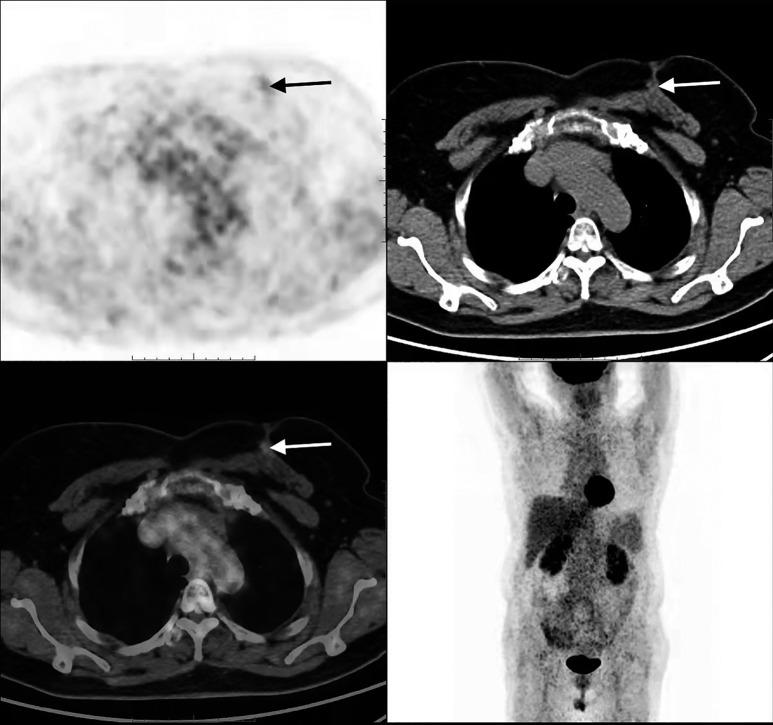

Unusual breast metastasis from follicular thyroid carcinoma 17 years after thyroidectomy: a case description and literature analysis.

https://cdn.ncbi.nlm.nih.gov/pmc/blobs/a744/11652007/2e811b53b089/qims-14-12-9796-f1.jpg